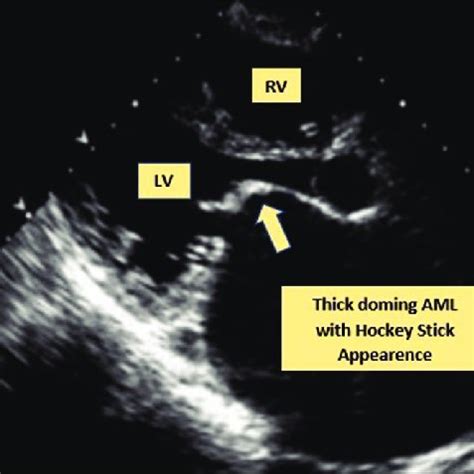

So, what exactly are we looking at when we talk about the hockey stick appearance in the context of Acute Myeloid Leukemia (AML)? Imagine peering through a powerful microscope at a sample of bone marrow or peripheral blood. You’re looking for abnormal cells, known as blast cells, which are immature white blood cells that have gone rogue in AML. Normally, these cells would mature into functional white blood cells, but in AML, they accumulate and don’t mature properly. The hockey stick shape is a specific morphological characteristic that some of these blast cells can display. It’s not just a vague resemblance; it’s quite distinctive. Typically, the nucleus of the blast cell appears elongated and curved, often with a deep indentation or fold. Think of the shaft of a hockey stick. Then, the cytoplasm extends from one end of this nucleus in a tail-like fashion, resembling the blade of the stick. This gives the cell a characteristic, elongated, and slightly hooked appearance. It’s important to understand that not all blast cells in an AML patient will show this morphology, and it’s not present in every single case of AML. However, when it is seen, it’s a significant finding for the hematopathologist. This specific shape is thought to arise from abnormalities in the cell’s cytoskeleton and nuclear structure , which are common features of malignant transformation. The cell loses its normal roundness and develops these irregular, elongated forms due to disruptions in the proteins that maintain cell shape and organization. The presence of the hockey stick appearance can sometimes suggest a particular lineage of AML, most commonly those with monocytic differentiation . This includes subtypes like acute monocytic leukemia (AMoL) or acute myelomonocytic leukemia (AMML). In these types of AML, the myeloid precursors have a tendency to develop more irregular and folded nuclear shapes, making the hockey stick morphology a more frequent observation. Recognizing this shape is crucial because it adds another piece to the diagnostic puzzle. It reinforces the presence of leukemic blasts and can help guide the pathologist in classifying the specific subtype of AML. This classification is absolutely critical, guys, because different subtypes of AML respond differently to various treatments. So, while we have advanced genetic and molecular tests today, the fundamental skill of recognizing classic morphological features like the hockey stick appearance remains a cornerstone of AML diagnosis. It’s a visual hallmark that, when identified by an experienced pathologist, provides valuable information that complements other diagnostic data, leading to more accurate and timely diagnoses and ultimately, better patient care. The detailed examination of cells under a microscope is a skill that has been refined over decades, and these classic descriptions, like the hockey stick appearance, are part of the specialized language pathologists use to describe and classify blood disorders. It’s a testament to the power of observation in medicine.

Alright, so we’ve established that the hockey stick appearance is a specific visual cue seen in some AML blast cells. But why is it such a big deal? Why do hematologists and pathologists get excited when they spot it? Well, its significance boils down to a few key points, all of which ultimately impact patient care and treatment. Firstly, and most importantly, the hockey stick appearance is a strong indicator of the presence of leukemic blasts . In the context of a suspected or confirmed diagnosis of AML, observing this morphology strongly supports the identification of immature, abnormal myeloid cells. This is crucial because AML is defined by the proliferation of these blasts. The more definitive clues we have pointing to blasts, the more confident we can be in the diagnosis. Secondly, this specific morphology can provide valuable clues about the subtype of AML . As mentioned, the hockey stick shape is particularly associated with myeloid leukemias that have monocytic features, such as acute monocytic leukemia (AMoL) or acute myelomonocytic leukemia (AMML). Recognizing this can help steer the diagnostic process. For instance, if a pathologist sees the hockey stick appearance, they’ll pay closer attention to other features that are characteristic of monocytic differentiation and might prioritize certain additional tests that are particularly useful for these subtypes. This subtype classification is super important because AML is not a single disease; it’s a heterogeneous group of cancers, and treatment strategies can vary significantly depending on the specific subtype. Some subtypes are more aggressive, some respond better to certain chemotherapies, and some might be candidates for targeted therapies. Therefore, any morphological feature that helps refine the classification is incredibly valuable. Thirdly, it underscores the importance of traditional morphological examination in the age of advanced diagnostics . We live in an era of incredible technological advancement in medicine, with sophisticated genetic sequencing, flow cytometry, and other molecular techniques now integral to AML diagnosis and classification. These tests provide a deep understanding of the leukemia’s genetic makeup, which is critical for prognostication and treatment selection. However, none of these advanced tests replace the fundamental role of the microscope and the expertise of the pathologist. The hockey stick appearance is a classic morphologic finding that has been recognized for decades. Its continued relevance highlights that morphology is often the first line of evidence and provides a crucial foundation upon which more complex diagnostic data is built. An experienced pathologist can often identify potential issues and guide the subsequent investigations based on what they see under the microscope. Finally, it contributes to a more comprehensive understanding of the disease process . The abnormal shape of these cells isn’t just a random artifact; it reflects underlying biological changes within the malignant cells. Understanding these morphological variations can sometimes offer insights into the cell’s behavior, its potential for infiltration, and its response to therapy. So, while it might seem like a subtle detail, the hockey stick appearance is a significant finding that aids in diagnosis, classification, and ultimately, in tailoring the most effective treatment plan for patients battling AML. It’s a classic example of how looking closely at the cells can tell us so much about the disease.